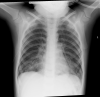

(A) Chest X-ray at presentation, showing the radiopaque food contact dust in the stomach (B) X-ray of food contact dust in original container (C) X-ray of radiopaque food contact dust on its own similar to what is seen in the patient’s stomach. AP, anteroposterior.

Chest X-ray taken less than 24 hours later, showing bilateral perihilar infiltrates extending into the lower zones.